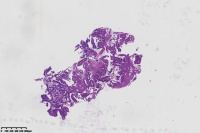

中分化腺癌?

性别

女

年龄

67岁

临床诊断

一般病史

直肠占位

标本名称

大体所见